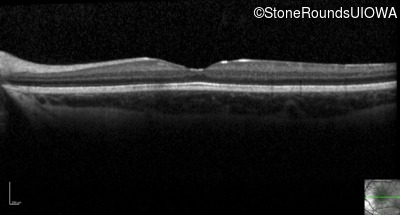

Optical Coherence Tomography - Right - 20/50 -1

Exemplar / OCT Stack